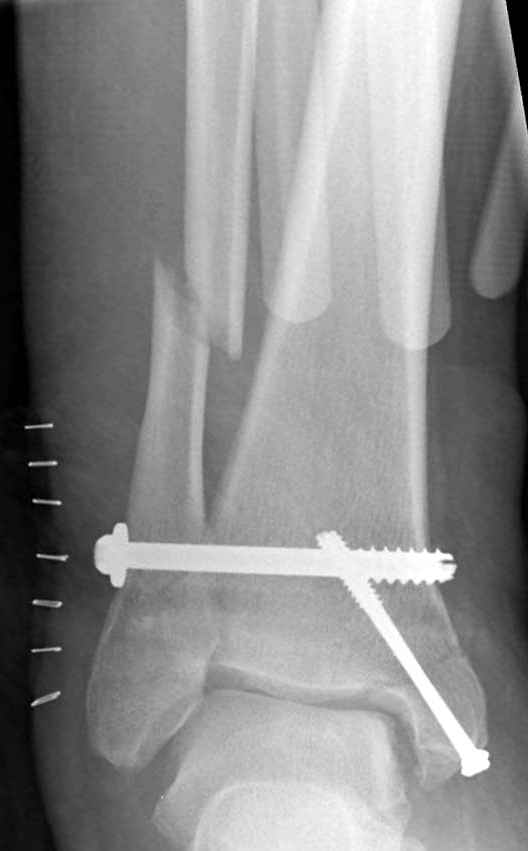

Недавний случай, больной 56 лет получил политравму в Англии, после переведен в США, где его успешно лечил местный ортопед, огромная статья в газете об успешной операции, своеобразный пиар, из-за того, что больной был американский пожарник на пенсии, и за его переезд было заплачено международным пожарным союзом, короче по другим показаниям перевели больного в наш университетский госпиталь.

После 5-6 недели после травмы сделана повторная операция, обошлись без удлинения малоберцовой.